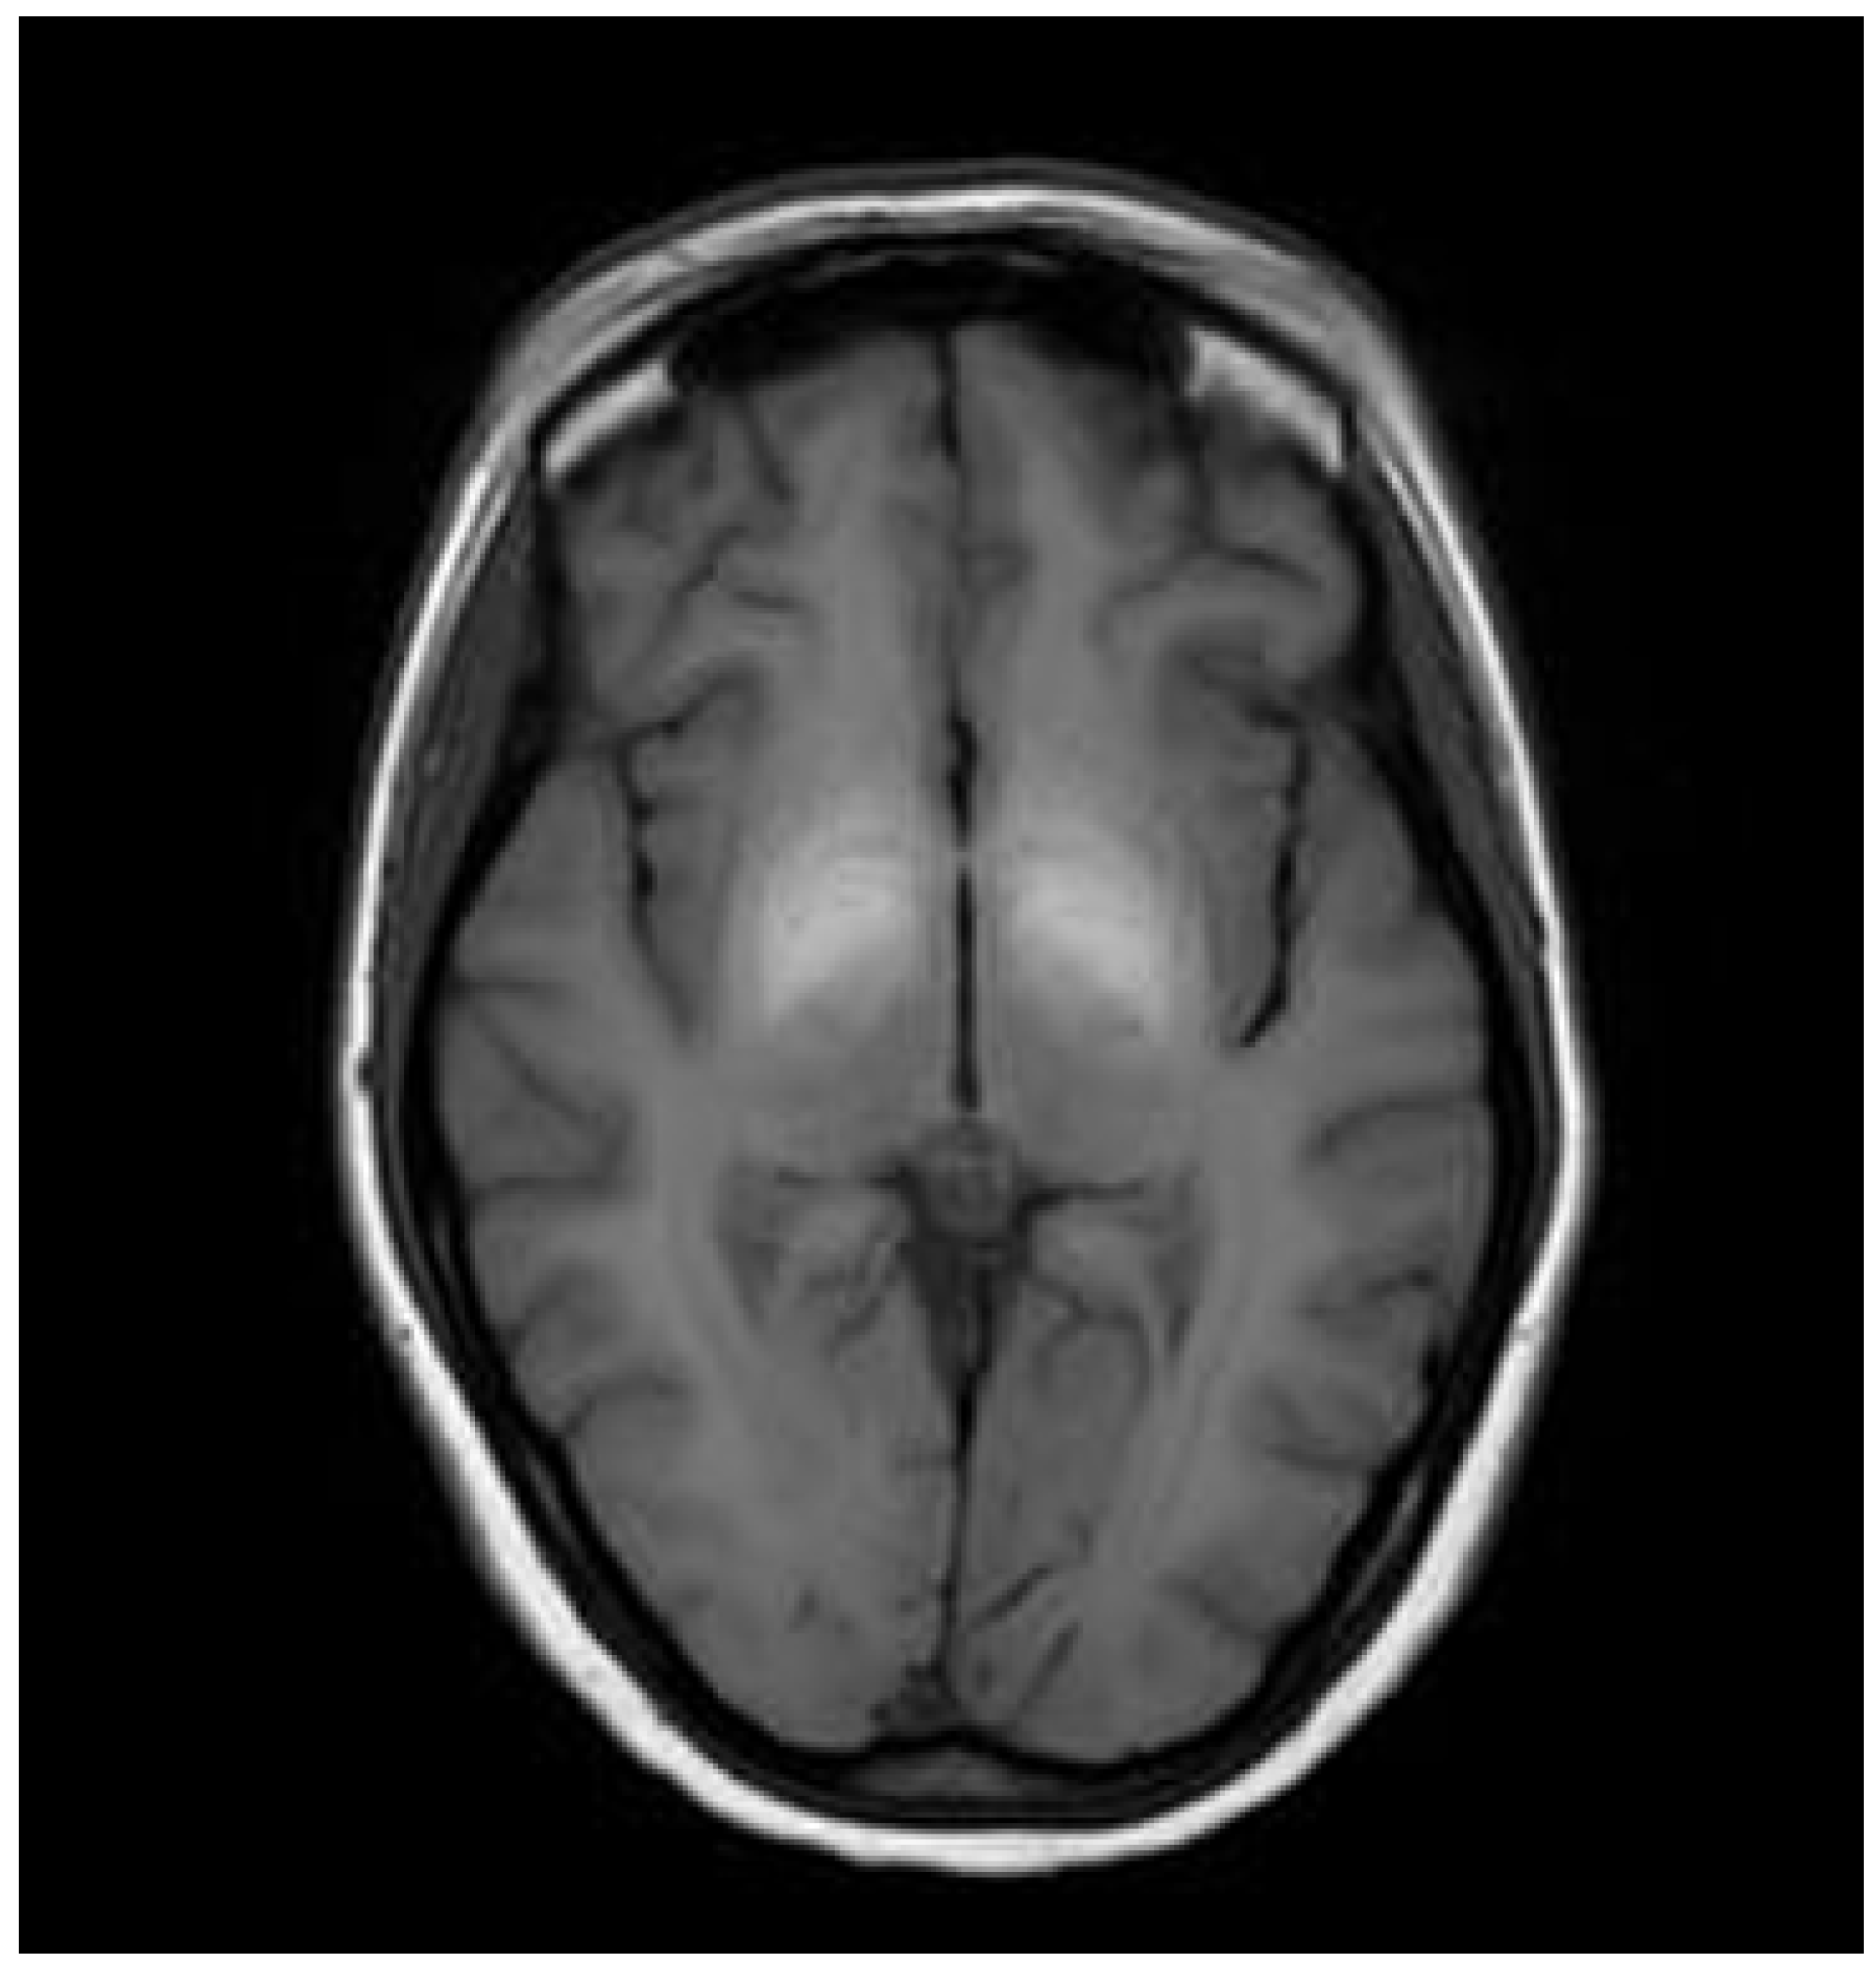

3.1. Classical Brain MRI Examination in WD Patients

5. Neuroradiological Pathognomonic Signs of WD